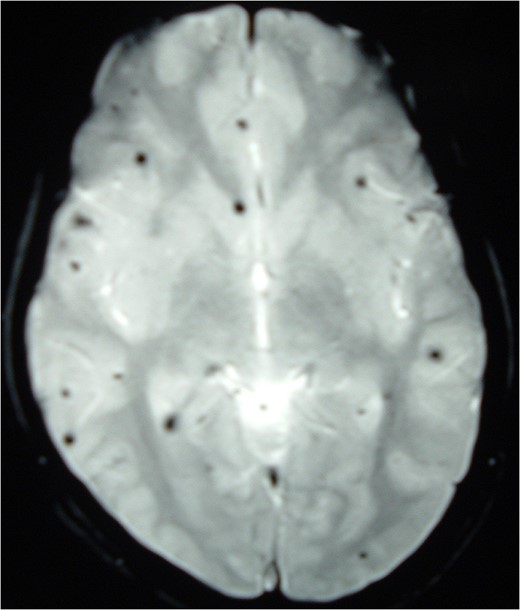

Magnetic resonance imaging (MRI) of the brain and spine showed multiple hypointense lesions in the brain and one mixed intense lesion with a hyperintense rim intrinsic to the spinal cord at the level of C5 with evidence of fresh bleeding (Figs 1–3). He was diagnosed with multiple cerebral cavernomas and an acutely bleeding spinal cavernoma. The patient was scheduled for a laminectomy and total excision of the spinal cavernoma and to control further hemorrhage. Bone removal was limited to the site of malformation. The lesion was identified by the bluish discoloration on the dorsal surface of the spinal cord (Fig. 4). A myelotomy was made over the discoloration and the lesion was excised inside out. Intraoperative evoked potential monitoring was not used for our procedure due to lack of availability.

MRI Brain (GRE T2WI) showing multiple hypointense lesions diagnosed as cerebral cavernomas.

Intramedullary spinal cavernomas may be associated with multiple concurrent occult cerebral cavernomas as seen in our case. This makes MRI of the complete neuraxis a crucial next step [1, 4, 5]. Familial CM syndrome should be suspected for any case with multiple cerebral cavernomas [4]. MRI remains the gold standard for diagnosing both cerebral and intramedullary cavernomas. They appear as mixed signal intensity lesions in on T1 and T2-weighted images surrounded by a low-signal intensity zone (due to hemosiderin deposits) best seen on T2-weighted images [4, 5, 8].